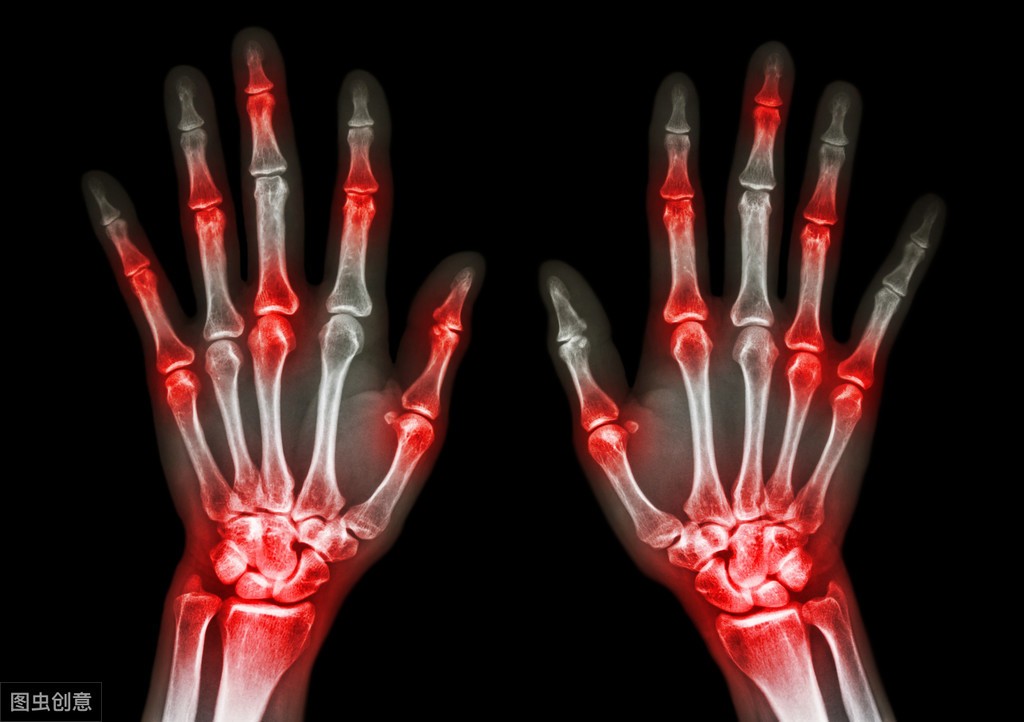

降尿酸的8种食物;香蕉,含有丰富的维生素、矿物质和果胶等膳食纤维,其中碱性成分、钾元素正是尿酸“终结者”。多吃香蕉可提高体内的碱性物质,中和由尿酸产生的酸性物质,可碱化尿酸,提高尿酸的溶解度,减少尿酸沉积,促进尿酸排泄。

芹菜有丰富的胡萝卜素、钾、食物纤维等营养元素,有效的防止人体尿液的积蓄,还有一定缓和控制高血压的效果。

百合在老中医眼里是一种好药。百合能健脾润肺,提高机体免疫力。对于高尿酸而言,百合中的大量生物碱可以中和体内的尿酸,从而大大降低尿酸含量。

黄瓜中的营养元素非常丰富,酶活性也比较高,经常吃点黄瓜,可能会促进机体的新陈代谢,促进血液循环,还可能加速体内尿酸的排出,对于痛风患者很有好处。

牛奶中含有丰富的钙质,以及大量的优质蛋白质,不仅仅对预防骨质疏松有好处,还对尿酸高以及痛风的人群有一定的益处。调查上发现,每天喝2杯多牛奶的人群要比不经常喝牛奶的人群,患上痛风的概率会降低到一半左右,一个星期之内喝了两次牛奶的人群还要比不喝牛奶的人群,患上痛风的概率会降低到3/10,但这里要注意的是最好食用低脂的牛奶,这样不会影响机体脂肪的量。

莲雾是一种水果,应该有人吃过的吧,它的形状有点奇怪,但是水分多。经常是的话,有利尿的作用。尿酸高的人,多吃莲雾这种水果,能够很好的降低尿酸,所以别错过了。

鸡蛋中的蛋白质对肝脏组织的损伤具有修复作用,蛋黄中的卵磷脂可促进细胞再生,增强机体代谢功能和免疫功能;防治动脉硬化,用鸡蛋治疗动脉粥样硬化有着惊人的效果;防癌症,鸡蛋中含有较高的维生素B2,可以分解致癌物质,鸡蛋中的硒、锌等也有防癌作用;可以延缓衰老。鸡蛋含有人体几乎所有需要的营养物质,而且基本不含嘌呤,所以称其为“理想的营养库”。每天保证一个鸡蛋,是痛风患者必不可少的。

颐年康宝元舒,百合味甘、性微寒,具有润肺止咳、清心安神、补中益气、清热利尿、清热解毒、凉血止血、健脾和胃之功效。